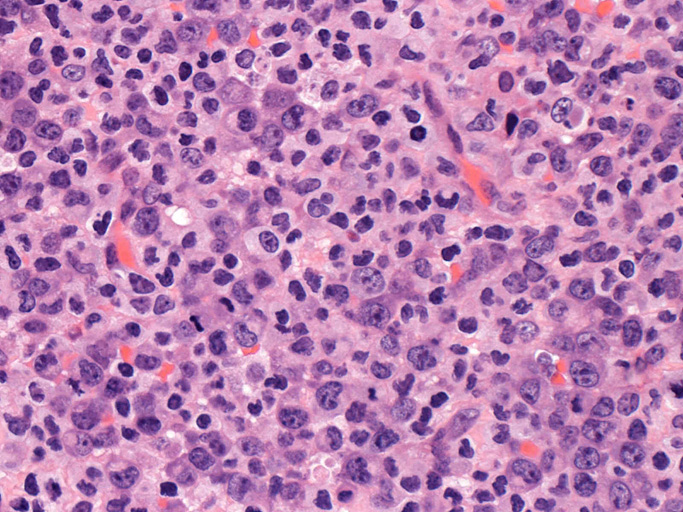

頸部リンパ節病理組織所見

いわゆるanaplastic large cellと呼ぶ多型または腎臓型核をもった大型細胞の増殖はみられない。centroblastに似る円形, 卵円形, わずかに切れ込みをもつ核をもつ大型細胞が索状または地図様に集ぞくし, 背景には淡明な細胞質としわのよったhypercrhomaticな核をもつ細胞がシート状に認められる。二種類の細胞がHEでは認められる。

ALK-positive ALCLのvariant, lymphohistiocytic variantが近いと考える